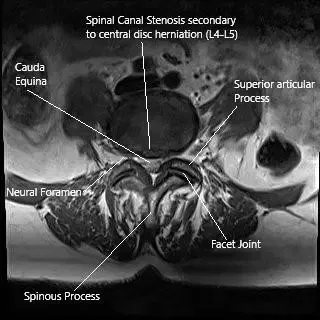

Resonancia magnética de la columna lumbar en una hernia discal central en la sección axial.

- Resonancia magnética: El estándar de oro para diagnosticar hernia de disco, compresión nerviosa o anomalías de tejidos blandos.